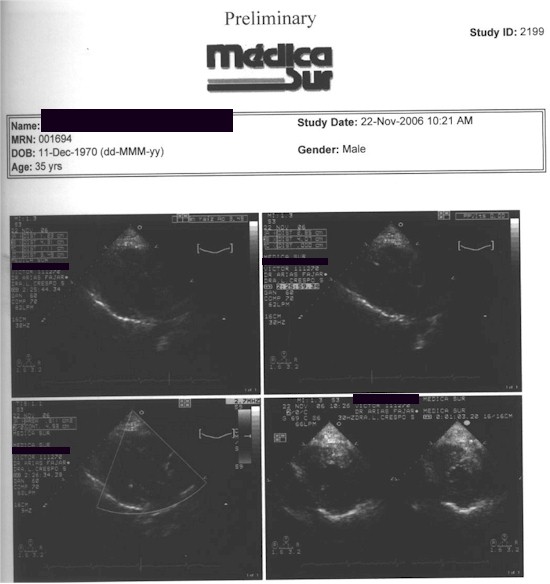

Sindrome de Breijo. Caso Clinico 8.